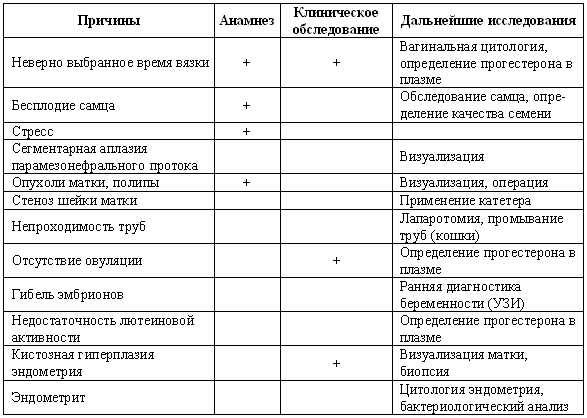

Табл. 3.1. Определение фазы репродуктивного цикла и некоторых патологий репродуктивного тракта по проявлению активности эстрогенов (определяется по вагинальной цитологии) и концентрации прогестерона в плазме

+ присутствует; — отсутствует